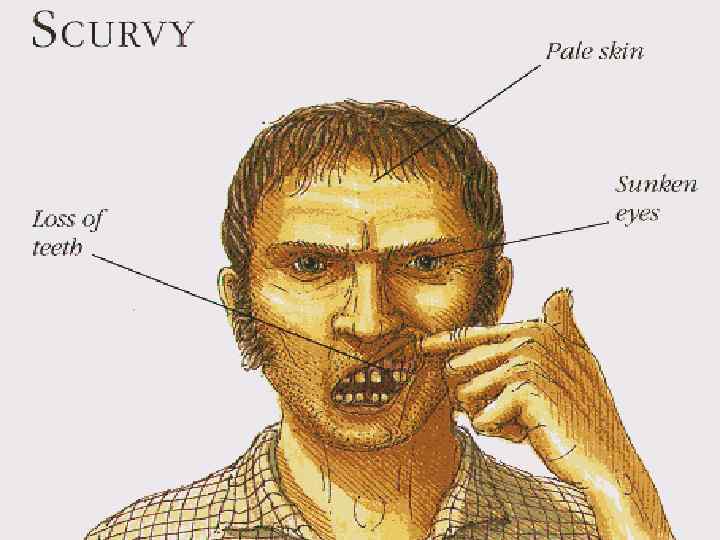

WATER SOLUBLE vitamins VITAMIN C: Found in oranges, lemons, tomatoes and green vegetables. • It`s deficiency in body causes scurvy.